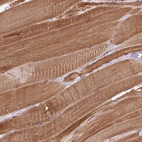

Immunohistochemical staining of human skeletal muscle shows strong cytoplasmic positivity in myocytes.